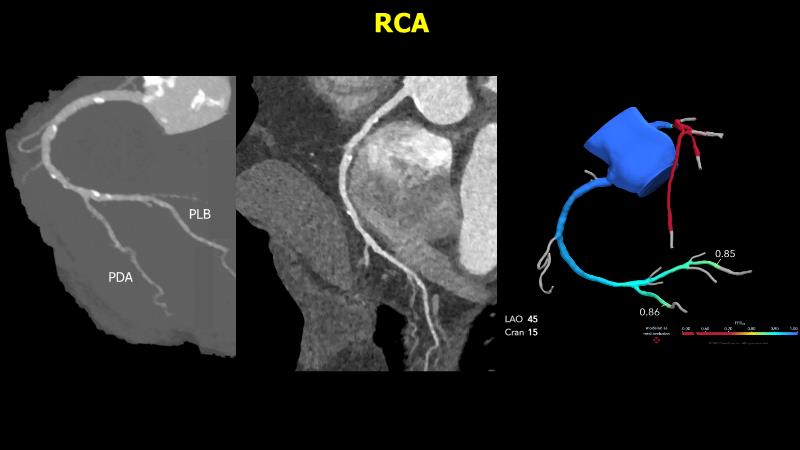

In this session, experience a multimodality approach, including CTA, angiography and OCT, and learn how to reestablish good hemodynamic of the bifurcation, by analyzing the case of an 81-year-old man with no risk factors, no relevant comorbidities, and no treatment, who presented with crescendo effort angina.

- To learn how to assess anatomy and physiology of left main lesion on non-invasive imaging